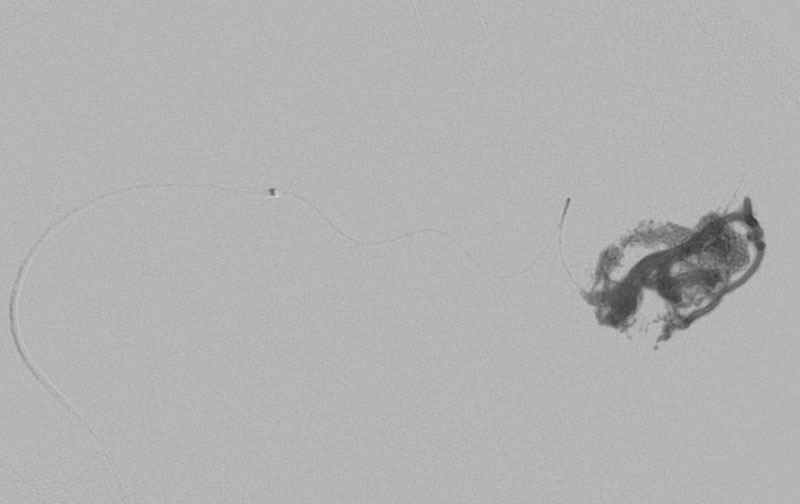

'26年3月

出血性脳動静脈奇形

10代

院内外来

No.1620 手術前

No.1620 手術中

No.1620 手術後